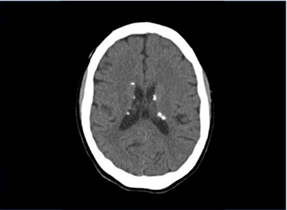

Menina, 4 anos, é trazida à consulta por crises convulsivas. Na avaliação, apresenta atraso de linguagem e, ao exame clínico, observam-se máculas hipopigmentadas em regiões lateral direita de abdome, perna direita, inguinal esquerda e dorso (fig.1). Observam-se nódulos eritematosos em região malar bilateralmente e dorso de nariz (fig.2). O exame de imagem apresenta nódulos subependimários (fig.3) e lesões em hiperdensas em parênquima cerebral. Apresentou síndrome de West no primeiro ano de vida.

Figura 1 Figura 2 Figura 3